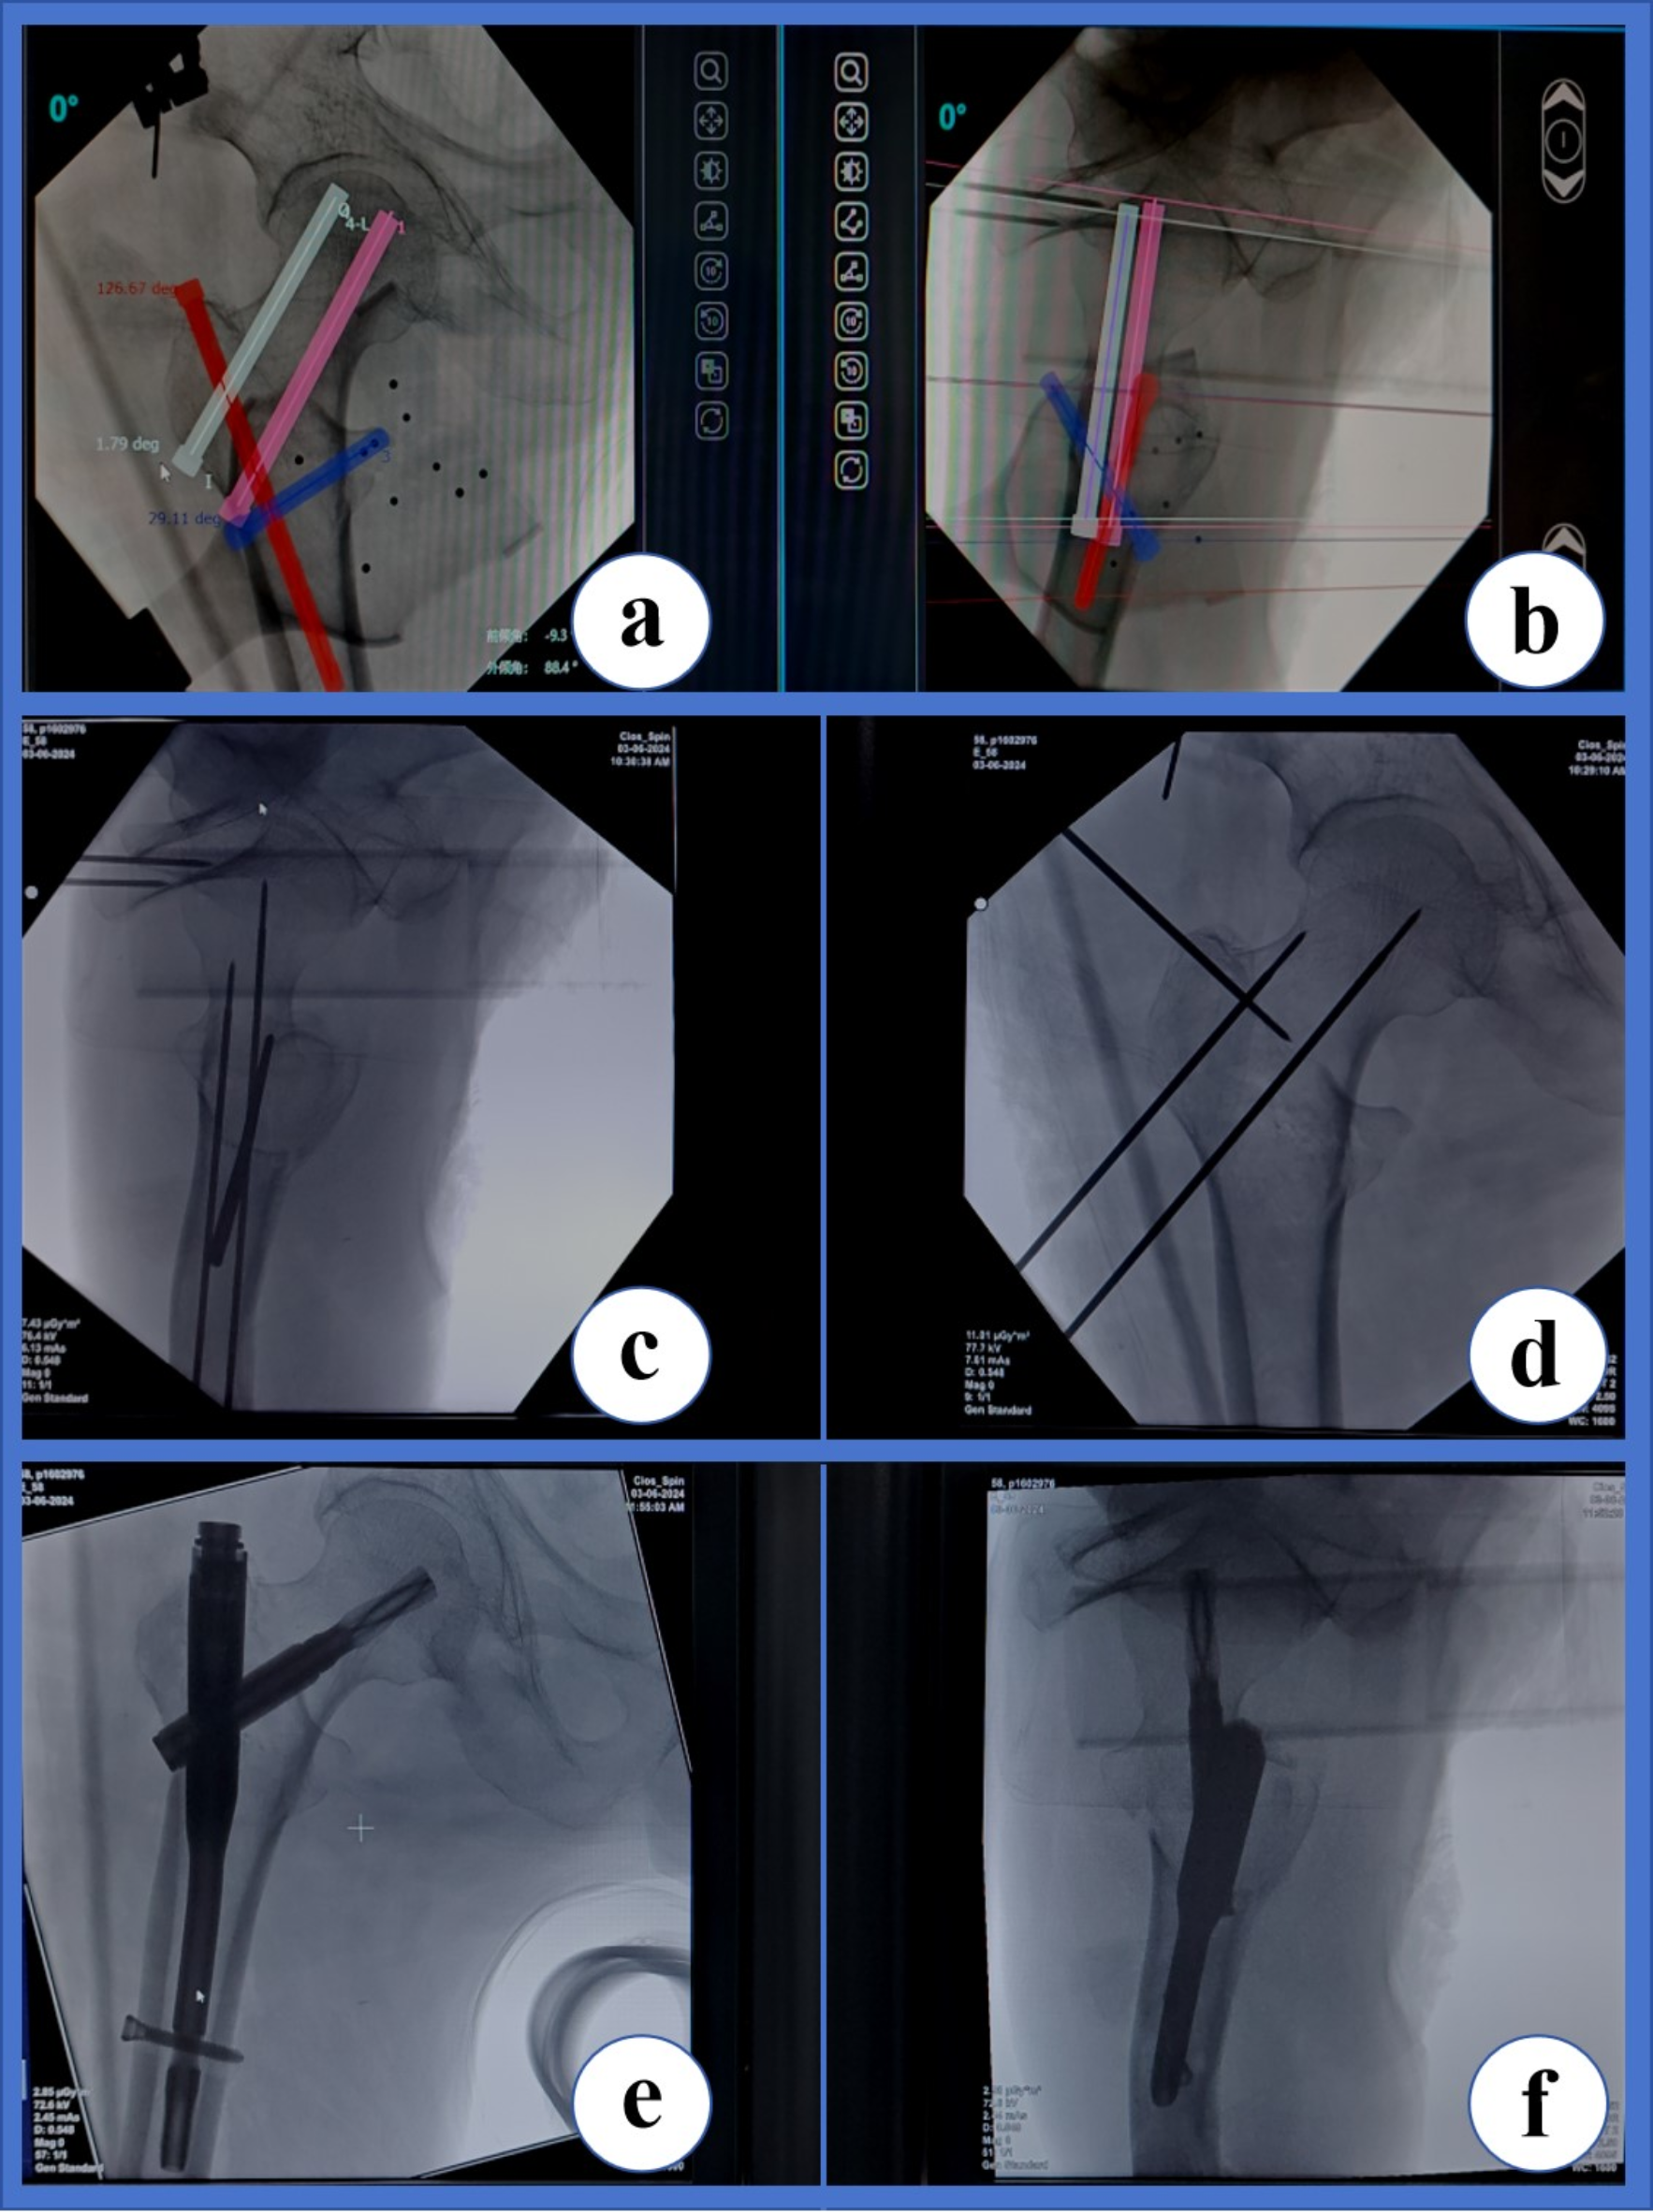

Fig. 1

Technical methods involving four guide pins by orthopedic robot-assisted PFNA surgery.(a, b), Planning the placement of the 1st guide pin (White) used to temporarily fix the fracture ends, planning the placement of the 2nd guide pin (blue) used to fix the lesser trochanter bone block, planning the placement of the 3rd guide pin (pink) used to guide the spiral blade, and planning the placement of the 4th guide pin (red) used to guide the main pin position. (c, d), With the assistance of the robot mechanical arm, these guide pins were placed under the guidance of anteroposterior and lateral fluoroscopy of the hip joint as needed. (e, f), Finally, under the guidance, PFNA was implanted and the results were verified by fluoroscopy.